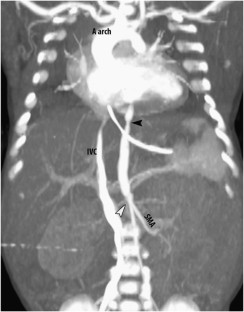

We report mid-aortic syndrome (MAC) in two preterm infants. Both infants developed malignant hypertension refractory to medical therapy and died early in infancy. Thus far, this account is of the two youngest patients with MAC.

Izraelit, A., Kim, M., Ratner, V. et al. Mid-aortic syndrome in two preterm infants. J Perinatol 32, 390–392 (2012). https://doi.org/10.1038/jp.2011.130